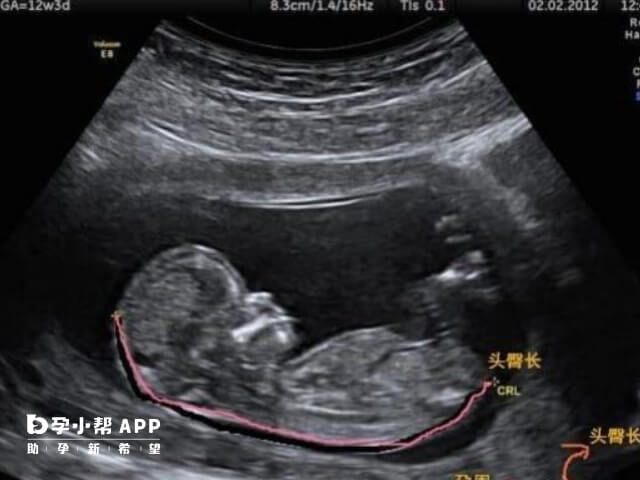

在孕12周的时候,孕妈妈们就需要上医院进行产检,产检的项目也是比较多的,其中就包括胎儿的头臀长,之所以这里要提到胎儿头臀长,是因为现目前很多的孕妈妈会通过这个数据来判断胎儿是男是女。网传说的是,如果在孕12周,是通过胎儿头臀长58mm进行判断的。那么事实到底是怎么样的呢?今天就全面的给大家分析分析这个准不准,看看实际的情况。

简单来说,头臀长和胎儿性别并不存在对等关系。孕12周胎儿的头臀长大概在5-6cm,偏多偏少一些都属于是正常的。很多人都觉得数值越大,就代表是男孩,数值越低就代表是女孩。其实不然,胎儿的大小以及四肢长短与遗传有关系,还与孕妈孕期的营养状况有关,和胎儿性别是没有关系的,因此12周nt头臀长不能够看出男女。所以姐妹们要理性的看待,不要去相信这些没有科学依据的传言。